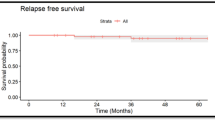

At the time of this writing, 34 were alive and free of the primary disease, recurrence, or the development of secondary neoplasms other than cavernous angioma; 5 died of recurrence, 1 died of secondary leukemia, and 1 was alive with recurrence of the primary disease. Following irradiation treatment, 11 patients developed 19 cystic malacia during a median course of 30.8 months with a range from 14.9 to 59.3 months (Fig. 1). The site of predilection for cystic malacia was white matter around trigone of lateral ventricles with the incidence of 47.4% (9 of 19 lesions, 7 in 11 patients). Even two of our patients with posterior fossa tumors developed cystic malacia around trigone of lateral ventricle. Other sites for development of cystic malacia were as follows: five in frontal, two in parietal, two in temporal, and one in cerebellum. Children treated at an age younger than 4.5 years developed cystic malacia significantly earlier than those who were at least 4.5 years old (Fig. 2; median 32.2 months vs not reached, P = 0.0169, log-rank test).

Comparison of cystic malacia with cavernous angioma and white matter degeneration in the same patient group (Fig. 4) revealed that the incidence of cavernous angioma after high-dose cranial irradiation increased progressively, while that of cystic malacia did not increase after 5 years. White matter degeneration developed earlier than cystic malacia or cavernous angioma. Development of these three entities was mutually exclusive, and there was no association between the site of occurrence of cystic malacia and that of white matter degeneration or cavernous angioma. Representative cases are shown in Fig. 5a–c.